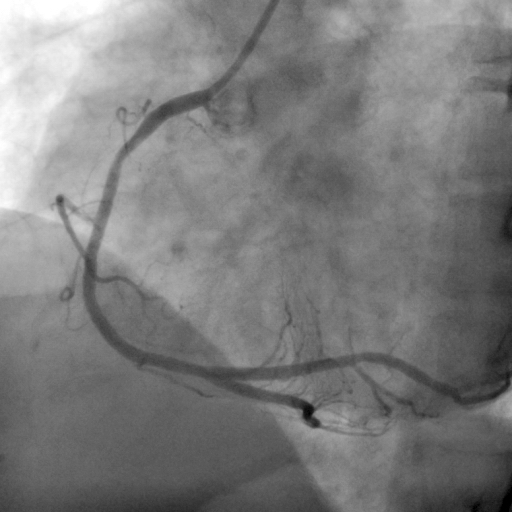

Koroner gaz embolisi, uçucularda düşük basınç ortamına maruz kalındığında görülebilir. Atmosfer basıncındaki hızlı düşüşlerde dokularda ve damarlarda açığa çıkan azot gazı kabarcığının (bubble) boyutu dış basınç düştükçe artar; ancak klinik bulgu vermeyen “sessiz kabarcıklar” da vardır. Bunlar dolaşımda 3 güne kadar kalabilmekte ve bu sürede emboli riski devam etmektedir. Uçuşta veya sonrasındaki 72 saat içinde ani başlayan göğüs ağrıları, sol kol uyuşmaları, bayılma, bilinç bulanıklığı gibi belirtiler kalp dekompresyon hastalığının habercisi olabilir. Böyle bir durumla karşılaşıldığında öncelikle damar sertliğine bağlı tıkayıcı kalp damar hastalığı düşünülür ve koroner anjiyografi planlanır, halbuki koroner gaz embolisi tanısı konursa, kişinin acilen yüksek basınçlı oksijen tedavisine alınması ile yaşamı kurtarılabilir.

Eskişehir Hava Hastanesinde alçak basınç (hipobarik çember) eğitiminden yaklaşık 24 saat sonra, genç bir jet pilotunda koroner gaz embolisine bağlı kalbin alt ve yan duvarını tutan bir kalp krizi gelişimi izlenmiştir. Bu pilotun EKG’sinde MI bulguları görüldükten sonra hemen hiperbarik oksijen tedavisine alınmış ve belirtilerin süratle düzelmesi nedeniyle tanının kalp DKH olduğu sonucuna varılmıştır (3).